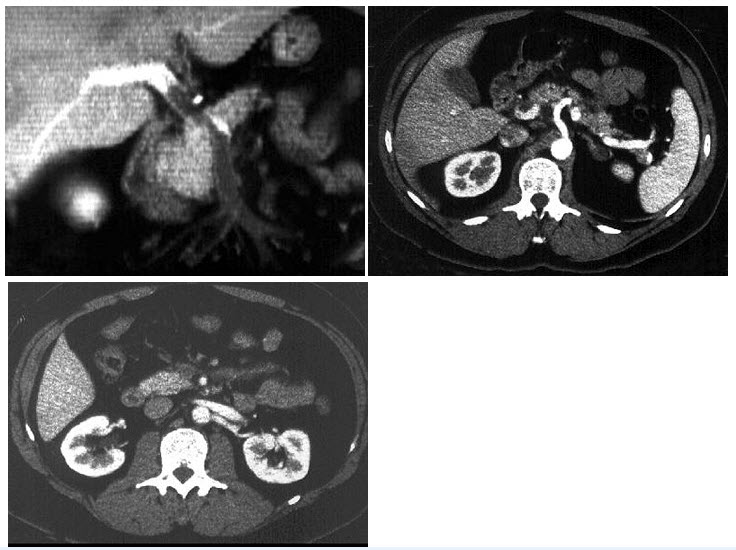

37、多项选择题

男,53岁,无痛性血尿2个月余,CT扫描如图示,下列说法正确的是()